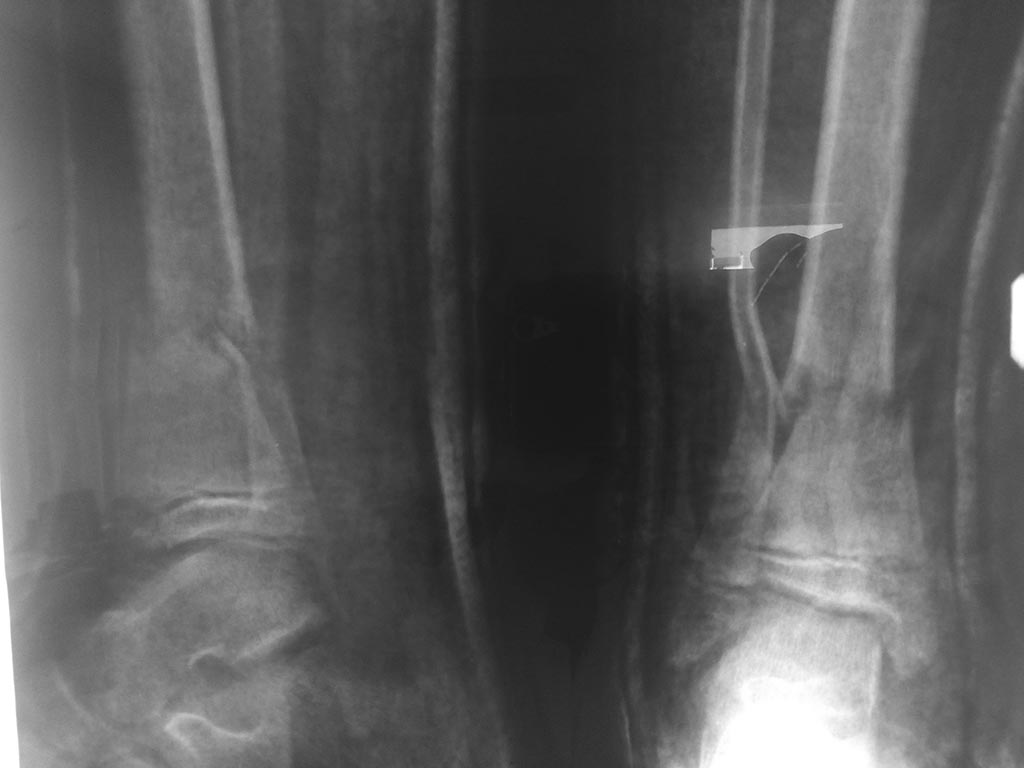

Допустимо ли стояние отломков касательно ребенка 2006г.

Подрепонировать бы стоило, ось на 10 градусов кнаружи.

До 15 лет деформация 10-15 градусов корригируется спонтанно, если

не заинтересованы зоны роста. Но все-таки ось лучше приблизить к нормальной.

Согласен, есть, для данного случая, приемлемая ссылка на Котельникова. Но, имеется ступенеобразная деформация эпифиза, угловое смещение... Наряду с этим, сотни учёных, в неком городе Кургане, потратили годы. чтобы доказать и показать эффект от применения чрескостного остеосинтеза при таких повреждениях. Фиксация в аппарате 6 недель и результат будет совсем другой. Воистину - Нет пророка в своём отечестве!!!

Да-да. И ступенеобразная деформация, и угловое смещение до 10 градусов... Глаз больше будет радовать рентгенкартина без угловых смещений и ступенеобразных деформаций. И отрепонировать можно. И плюс к репозиции спицами фиксировать. И аппарат можно наложить. И пластиной открыто синтезировать обе кости. И TENы загнать. Много вариантов существует, как помучить ребёнка, дабы порадовать своё травматологическое ЧСВ.